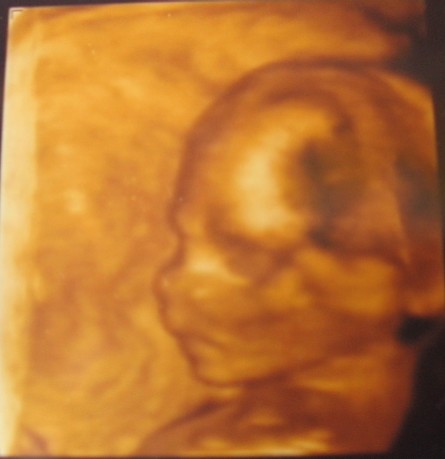

Ez a profil gyönyörű és nagyon megható!

Olyan kis finom, kedves!

tegnap voltam UH-n, minden OK, legalábbis nem mondták, hogy nem, ma kezdem a 19- hetet (Vicky küldök frissebb adatokat priviben). Ujjjééé!

A nemét sajnos nem tudjuk, már megint a hátát mutatta nekünk, s rettentően fel volt háborodva, hogy zargattuk. Biztosan pihizett, pedig direkt olyan kaját ettem, amit én a helyében szeretnék...

De sebaj, október elejére úgyis kérek 4D-s időpontot, s akkor reméljük, nem lesz ennyire durci-murci vagy szégyenlős.